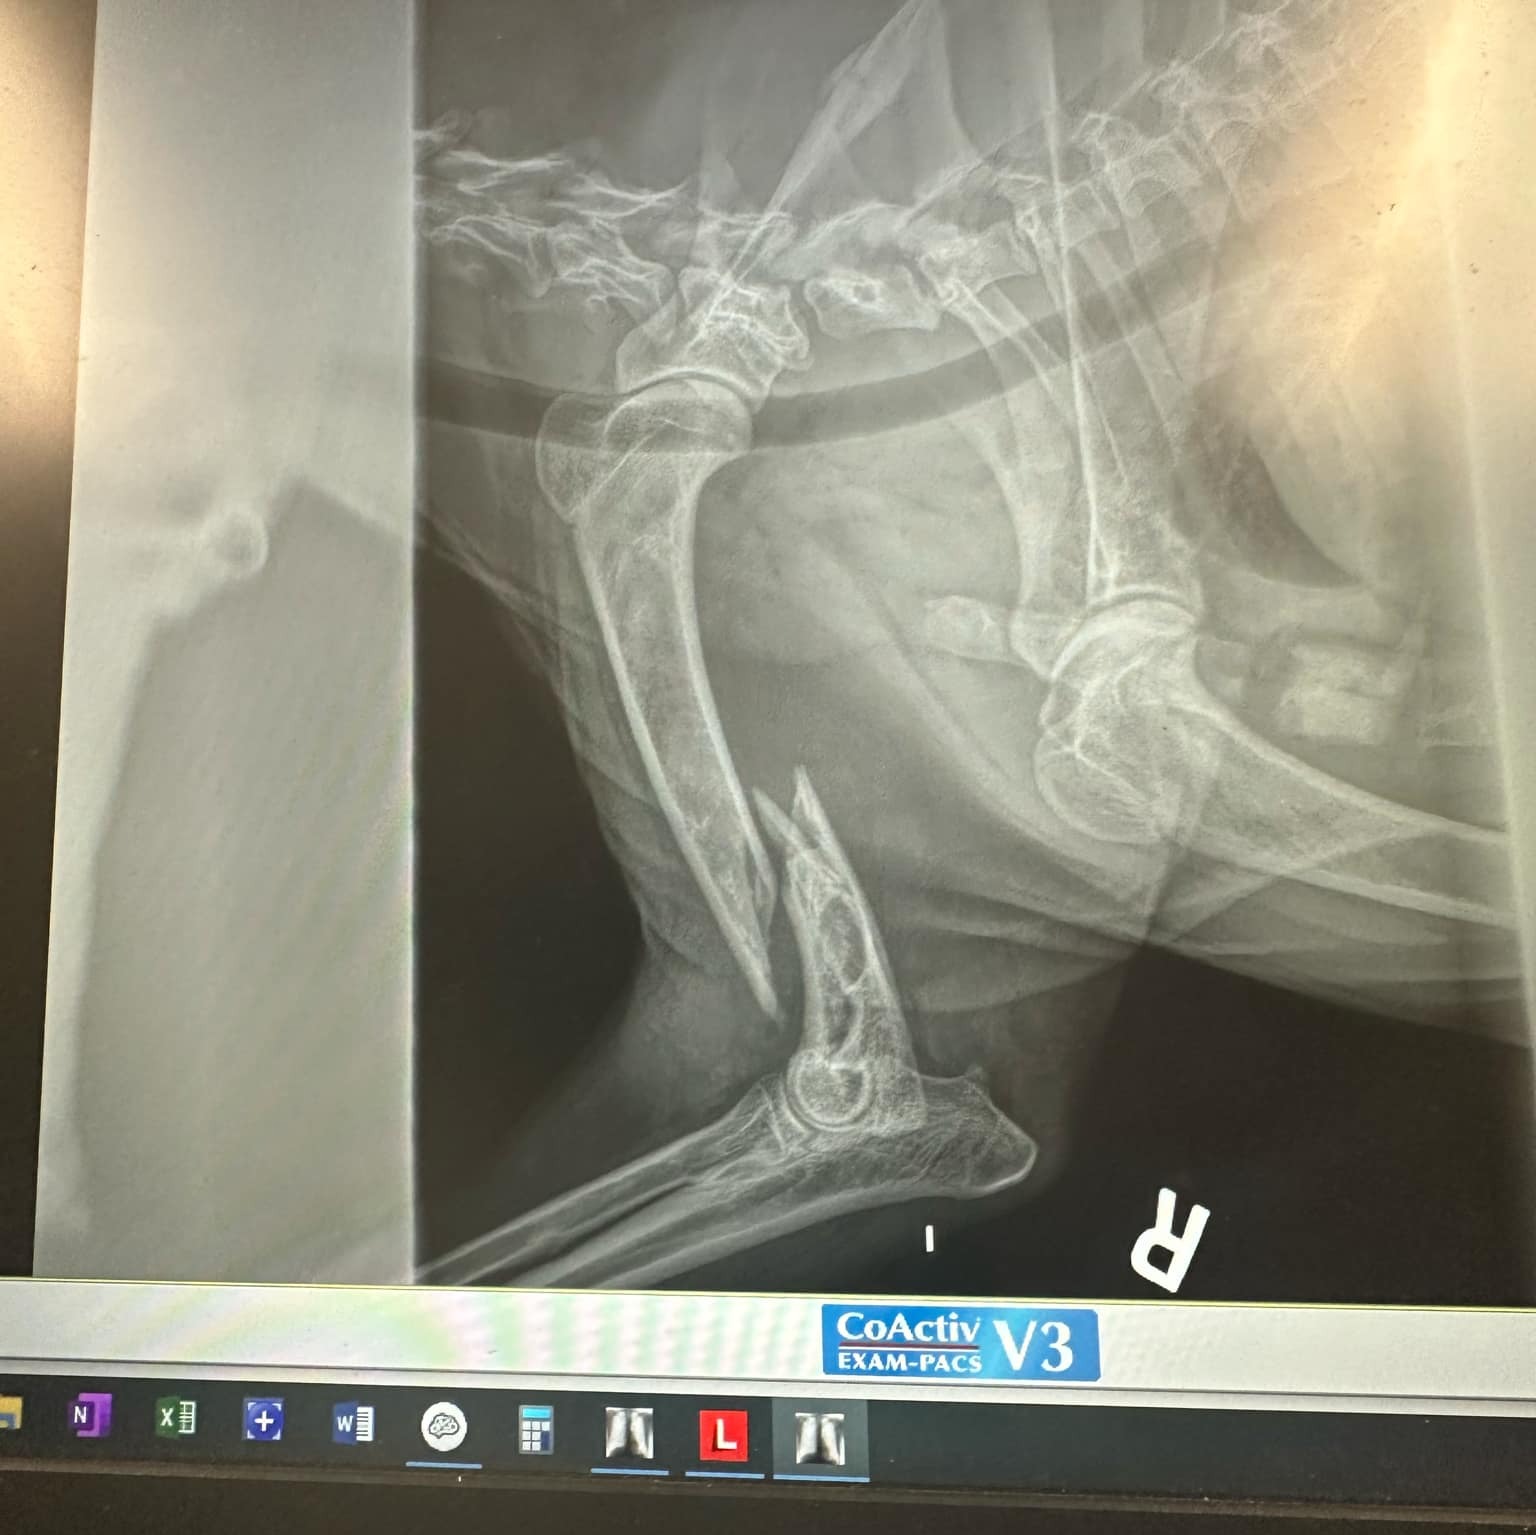

Finn is a special need rescue. We adopted him at 11 months due to the fact he couldnt be sold. He has a way of bunny hopping with his back legs. He was outside in a kennel and when we heard his story we just had to rescued him. He was just walking down the hill when he tripped and fractured his front leg. It is bad and they have discovered they may have found a tumor in the same leg. We are devastated. If this fundraiser raises enough to help us we will turn around and create a fund with VCA and Ocean State to help other pet parents in crisis just like I did with Autumns Fund while I was LACO. That fund helped so many animals and residents in need. Thank you to all who have donated. Its a rough time for all and we truly appreciate the help. John was laid off for 5 months so we were just getting back on our feet .